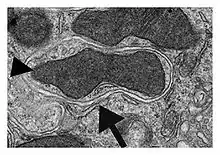

- La primera observación de una mitocondria en el interior de un autofagosoma fue realizada por Sam L. Clark en 1956 (publicada en 1957) en células renales de ratones recién nacidos.[15]

- En 1962 Ashford y Porter demostraron por primera vez de forma convincente la existencia de autofagia en hepatocitos, observando mitocondrias en autofagosomas.[16]